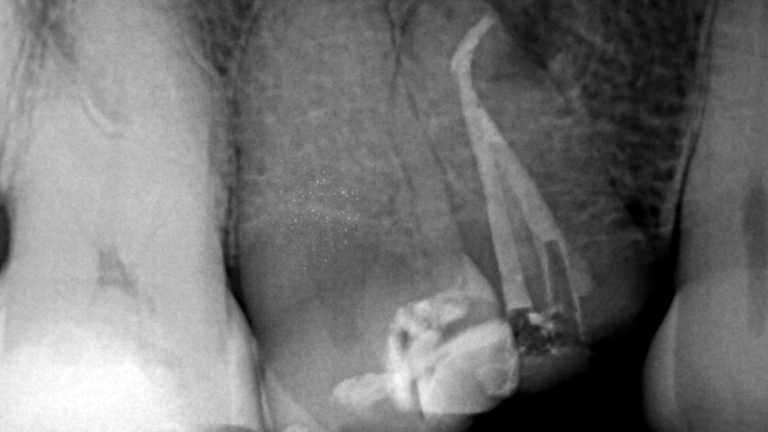

Caso clínico del doctor Marc Llaquet de una reendodoncia del diente 2.4 instrumentado con las limas RetreatAll® para…